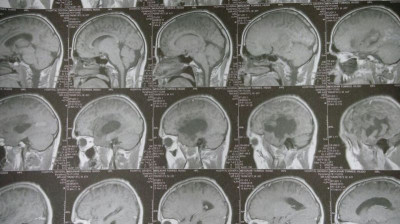

Oligodendroglioma temporal izquierdo Imagenes MRI Preoperatorio

Oligodendroglioma temporal Imagenes MRI Preoperatorio